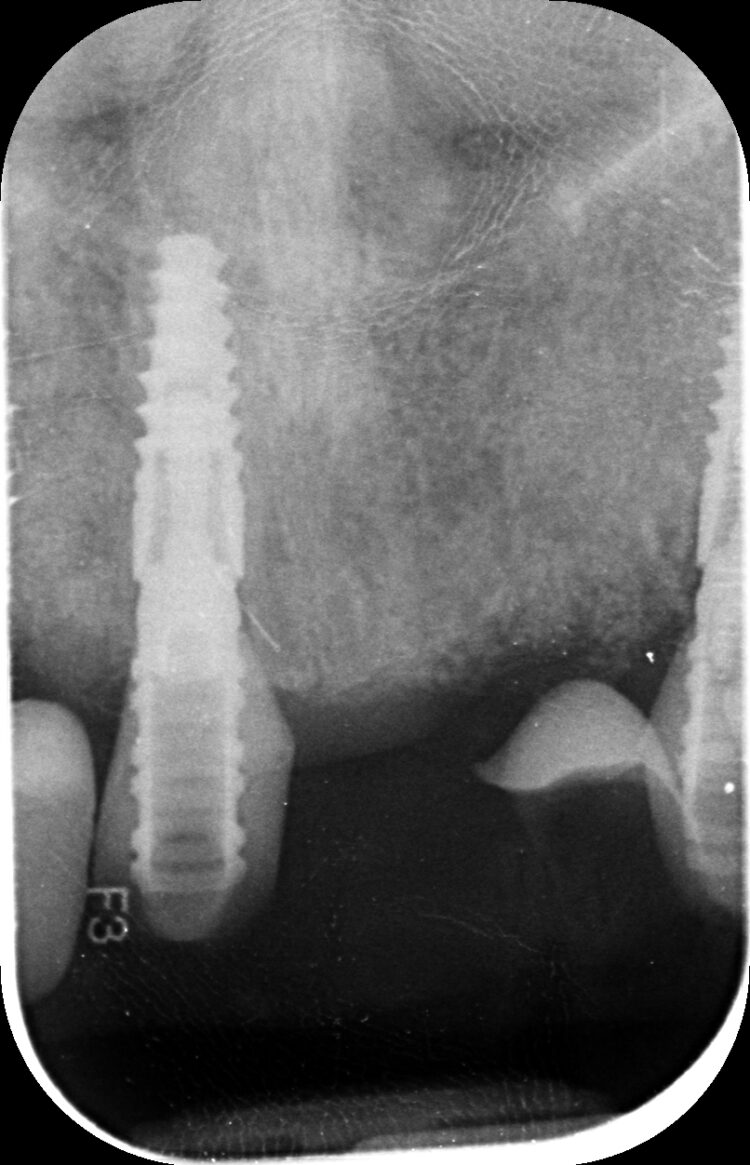

Despite using all the available examination tools, it was still challenging to assess the level of damage to the teeth under the metal ceramic bridge, because the prosthetic material obstructed the x-ray. It was confirmed that two teeth were decayed and fractured, but it was not possible to confidently diagnose the UR2.

The two 3.3mm diameter Tapered Pro Conical implants were then placed through the guide at the pre-determined positions, angles and depths. Both implants achieved an insertion torque above 30Ncm.

This new conical connection provides confidence that an optimal emergence profile will be achieved with the restoration, which is crucial when working in the aesthetic zone. The 3.3mm diameter implants were chosen; while wider implants are generally preferred, this case required a balance between utilising the available bone and adhering to natural structures, necessitating the use of narrower implants.